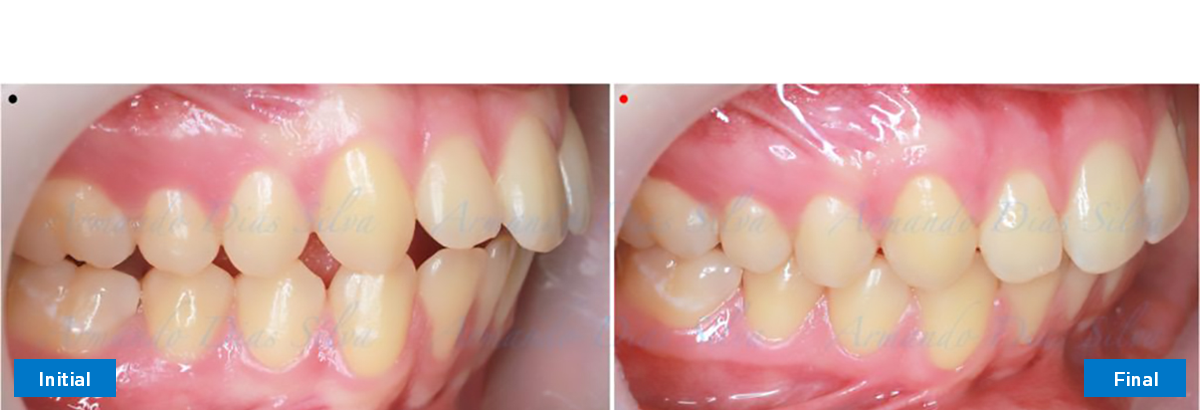

Clase II, Div. 1: Protrusión del incisivo central y espacios anteriores (SureSmile® Aligners)

Principal queja del paciente: Protrusión del incisivo central y mordida abierta. El paciente rechaza la expansión del arco palatino (MARPE) y las extracciones.

Este paciente adolescente presenta molares de Clase II y no le gusta su mordida abierta ni lo protrusivos que son sus dientes frontales. Por sus fotografías faciales, parece que su mandíbula es retrognática o le falta volumen en la barbilla. El historial del paciente también indica que existe un problema funcional al no haber guía de los incisivos.

• Molares de clase II

• Diastema

• Espaciamiento leve de las arcadas superior e inferior (deficiencia transversal de 3,45 mm)

• El primer molar superior derecho está en una posición más mesial que el primer molar superior izquierdo

• Deficiencia transversal maxilar leve (3,45 mm)

• Incisivos superiores e inferiores proclinados

• Orientación canina desfavorable

Se logran todos los objetivos principales:

• Molares de clase I logrados con distalización y sin elásticos

• Sin cambios en la posición del cóndilo

• Sin expansión maxilar, respetando la envoltura periodontal

• Incisivos inferiores retroinclinados, que mejoran la estabilidad a largo plazo

Retención: Arco superior retenido con retenedor transparente. Arco inferior retenido con retenedor lingual unido de canino a canino.